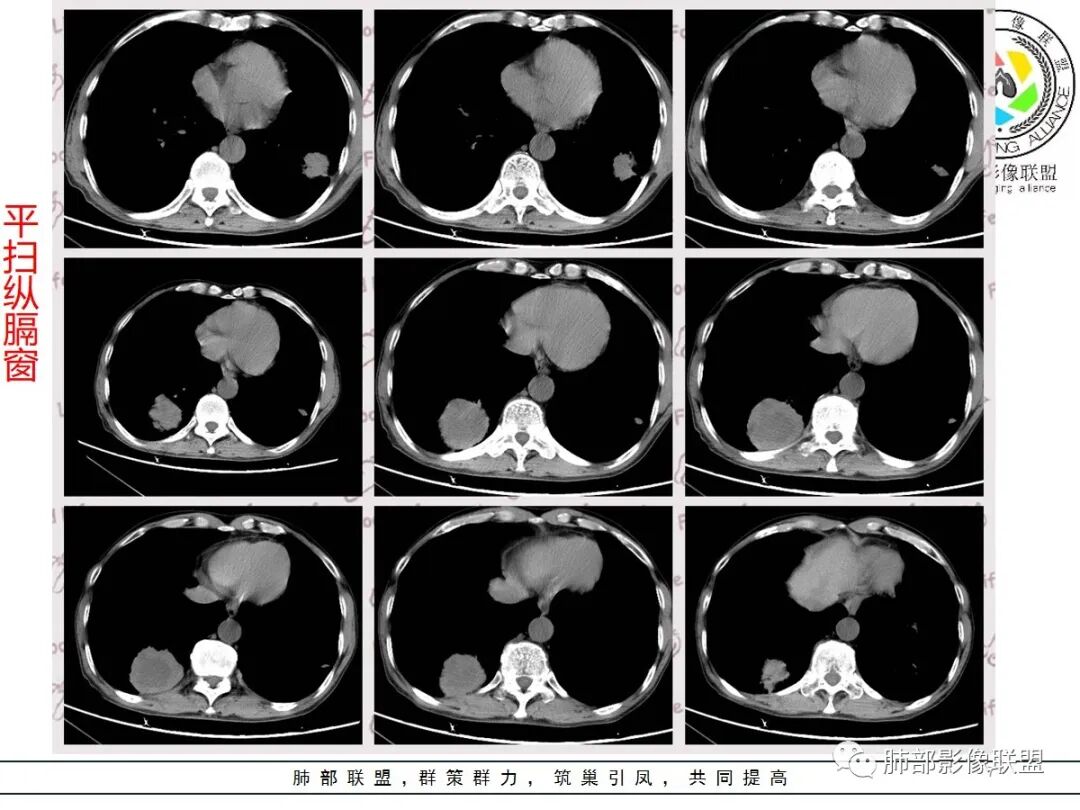

临床病史很长,背痛9年可能与左侧胸膜炎有关。两上肺陈旧性结核伴肺气肿没有问题。左下肺病灶,分叶毛刺、胸膜凹陷、指状凸起,增强轻度强化,腺癌问题不大。右侧附加题有些困难,病灶内血管显影,不像结核的表现,先把结核否掉?鳞癌和慢性脓肿的鉴别:支持良性的征像,低密度区内也有细小血管影,不像鳞癌坏死?与胸膜关系整体还是比较和谐,边缘还算光整,毛刺都在远端,不支持慢性脓肿的的地方,周围支气管管壁都很干净。恶性征像,与支气管的关系图片给的不够。坏死边缘不光整,有些浅分叶。总体,我觉得坏死区血管的存在更有价值,验证一下,右侧首先考虑慢性脓肿。

老年男性,结核、慢性病史,肺气肿背景,右肺胸膜下肿块影,边界清晰,边缘膨隆,中度环形强化,内见边界清晰坏死区,并见部分强化小血管,鳞癌破坏力强,而且病灶一侧支气管受推移,首先考虑右肺结核,鉴别鳞癌,左肺考虑腺癌,胸膜牵拉,膨隆生长,边缘毛刺样,潜在分叶。

老年男性,肺气肿背景,左肺下叶结节,深分叶,毛刺,胸膜牵拉,内部可见坏死,坏死边界不清,不均匀强化。右肺下叶大肿块,边缘有毛刺,多发小灶性坏死,胸膜下有侵犯,考虑恶性,左肺下叶腺癌,右肺下叶低分化鳞癌。

男,64岁,咳嗽咳痰,气喘10余年,右肺下叶软组织密度肿块影,边界清晰,边缘见细短毛刺及分叶,轻度胸膜粘连,病灶内密度不均,增强扫描看见坏死区,病灶边缘明显强化,考虑鳞癌可能。左肺下叶病灶深分叶、毛刺、胸膜牵拉,考虑腺癌可能,除外转移性病变。

双肺陈旧性肺结核,肺气肿背景。右肺下叶肿块,边缘毛糙,内部可见大片低密度坏死,环形强化,坏死边界清楚,考虑鳞癌。左肺下叶结节,边缘可见毛刺,深分叶,有收缩,有膨隆,胸膜牵拉,考虑腺癌。

右肺增强有强化,湖泊样坏死

右下肺穿刺,病理科医生考虑癌肉瘤,两种成分!

病理科老师当时来我们科讨论,就是有鳞癌和肉瘤两种成分呢,应该就是我们说的癌肉瘤或者肉瘤样癌一类

今天晨读我觉得最有特征性的就是那个强化,环状强化,周围强化比较明显的是癌,血供丰富,中间应该是肉瘤粘液变性,而且边界比较清楚,这个也算肉瘤样癌比较有特征性的,其他的跟其他恶性确实不好鉴别

主要征象:病灶分叶不明显、较光整,局部胸膜栽赃,支气管门口堵塞,有推移迹象;增强后坏死明显,内部囊变坏死边缘部分清楚、部分不清楚,病灶内可见血管,局部稍毛糙,实性部分强化较明显,总体考虑恶性病变。一部分征象指向鳞癌(支气管截断、坏死较多,病灶内血管破坏),但又有肉瘤的一些特点(病灶较大,缺乏分叶,坏死边界清晰),要考虑到肉瘤样癌。

3、本病好发于60岁以上的老年男性,多数有吸烟史。周围型多于中央型,病灶边缘较清楚,多数光整圆钝,部分可见浅分叶,少数有毛刺,无胸膜凹陷征出现。CT平扫时呈软组织密度,较小的肿块密度较均匀,肿块较大时中央常出现坏死。增强扫描肿块多呈斑片状不均匀强化,而肿瘤周边厚薄不均的囊壁样强化较具特征性。周围型多数位于胸膜下,常常侵犯胸膜或胸壁。